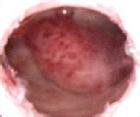

宫颈息肉给女性朋友的健康带来了很大的威胁,严重影响着患者朋友的正常工作和生活,为了减少宫颈息肉的发生,因此要积极做好此疾病的预防工作。那么,如何才能有效预防宫颈息肉呢?下面我们就来了解一下吧!